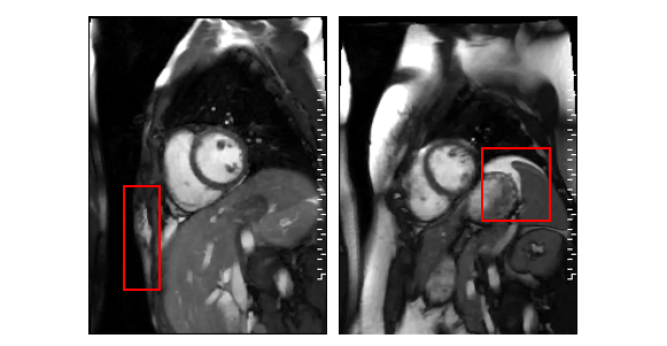

The motion in a manually selected region-of-interest (ROI) was used as a reference for the respiratory motion. As shown in Fig. 2, for each slice, the ROI was placed manually in an area with visually pronounced respiratory motion. The frame-to-frame motion was captured using non-rigid image registration [7]. To this end, all frames for a given slice were registered to the first frame to produce 2D deformation fields with horizontal and vertical components. The deformation field characterized the motion of each pixel across frames. The respiratory signal was extracted by averaging the horizontal or vertical component of the deformation field within the ROI. The appropriate component of the deformation field was selected based on the visual assessment of the motion within the ROI. For example, for the ROI selected on the liver dome, the component of the deformation field in the head-foot direction would be chosen. Agreement between the respiratory signal from the proposed method, , and the reference was evaluated using correlation coefficients. When the correlation was positive, the sign determination was considered to be correct.